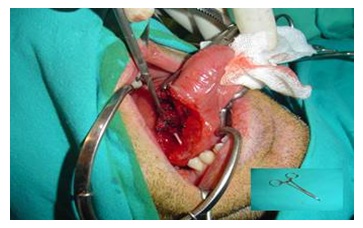

A thirty-year-old male without any previous medical history came to the accident and emergency department, at the General Hospital of the main city of this area. He complained of mouth pain. There was a large tuna fish bone on the mid right dorsal border of the tongue, which was removed. A few days later, he represented with a painful swelling of the tongue. A glossal abscess was aspirated with a large bore needle. An oral wide spectrum antibiotic and a non-steroidal anti inflammatory drug were prescribed. Two weeks later he returned with an increased tongue swelling without compromising the airway which showed a deep lesion in the lingual muscle (Figure 1&2) to the left of the midline Under general anaesthesia a wide incision of the lesion on the ventral tongue the direction of Wharton’s and further dissection of the former abscess opening. A silicone drain was left in place and the incision closed by three stitches. The patient improved a few hours after, and the episode resolved completely without any further complications (Figure 3&4).

Figure 3

Figure 3: Intraoperatorie view of the fish bone (arrow).

Figure 4

Figure 4: The fish bone near to a forceps.